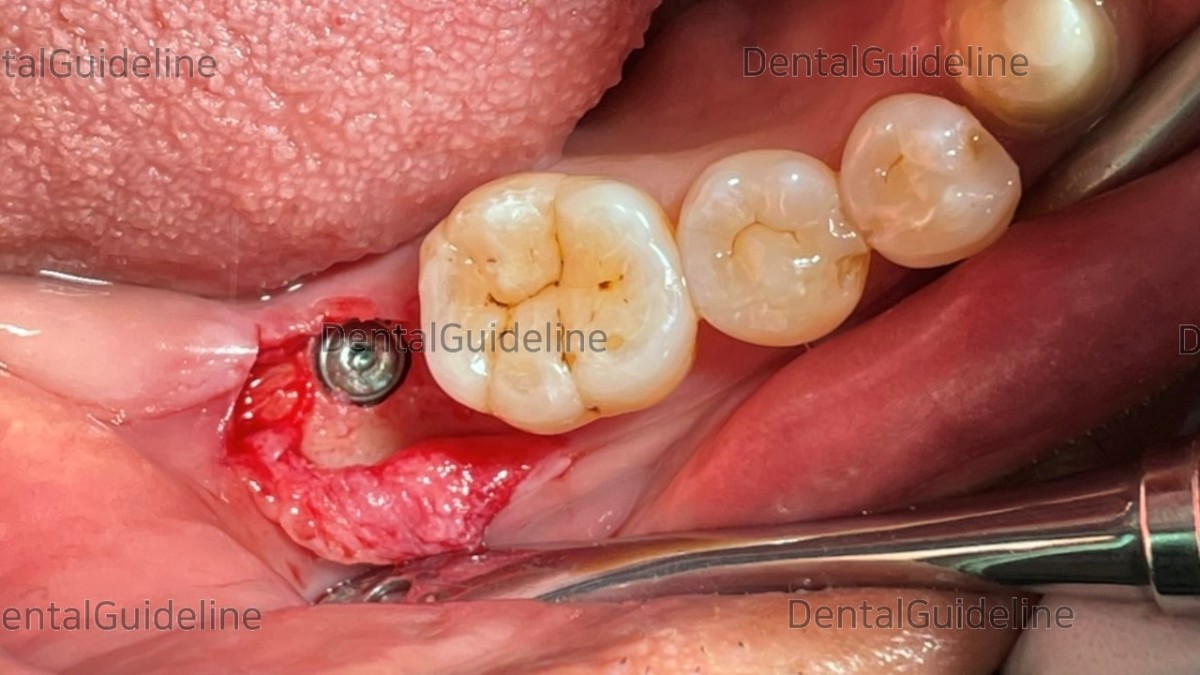

- Intra-oral view after extraction.

- Osteotomy (serial drilling but under-drilling).

- Arum Implant NB1 Ø5.0*L11.5mm.

- fixture placement.

- Check the initial stability (50Ncm).

-Collagen membrane and HA.

- Suture.